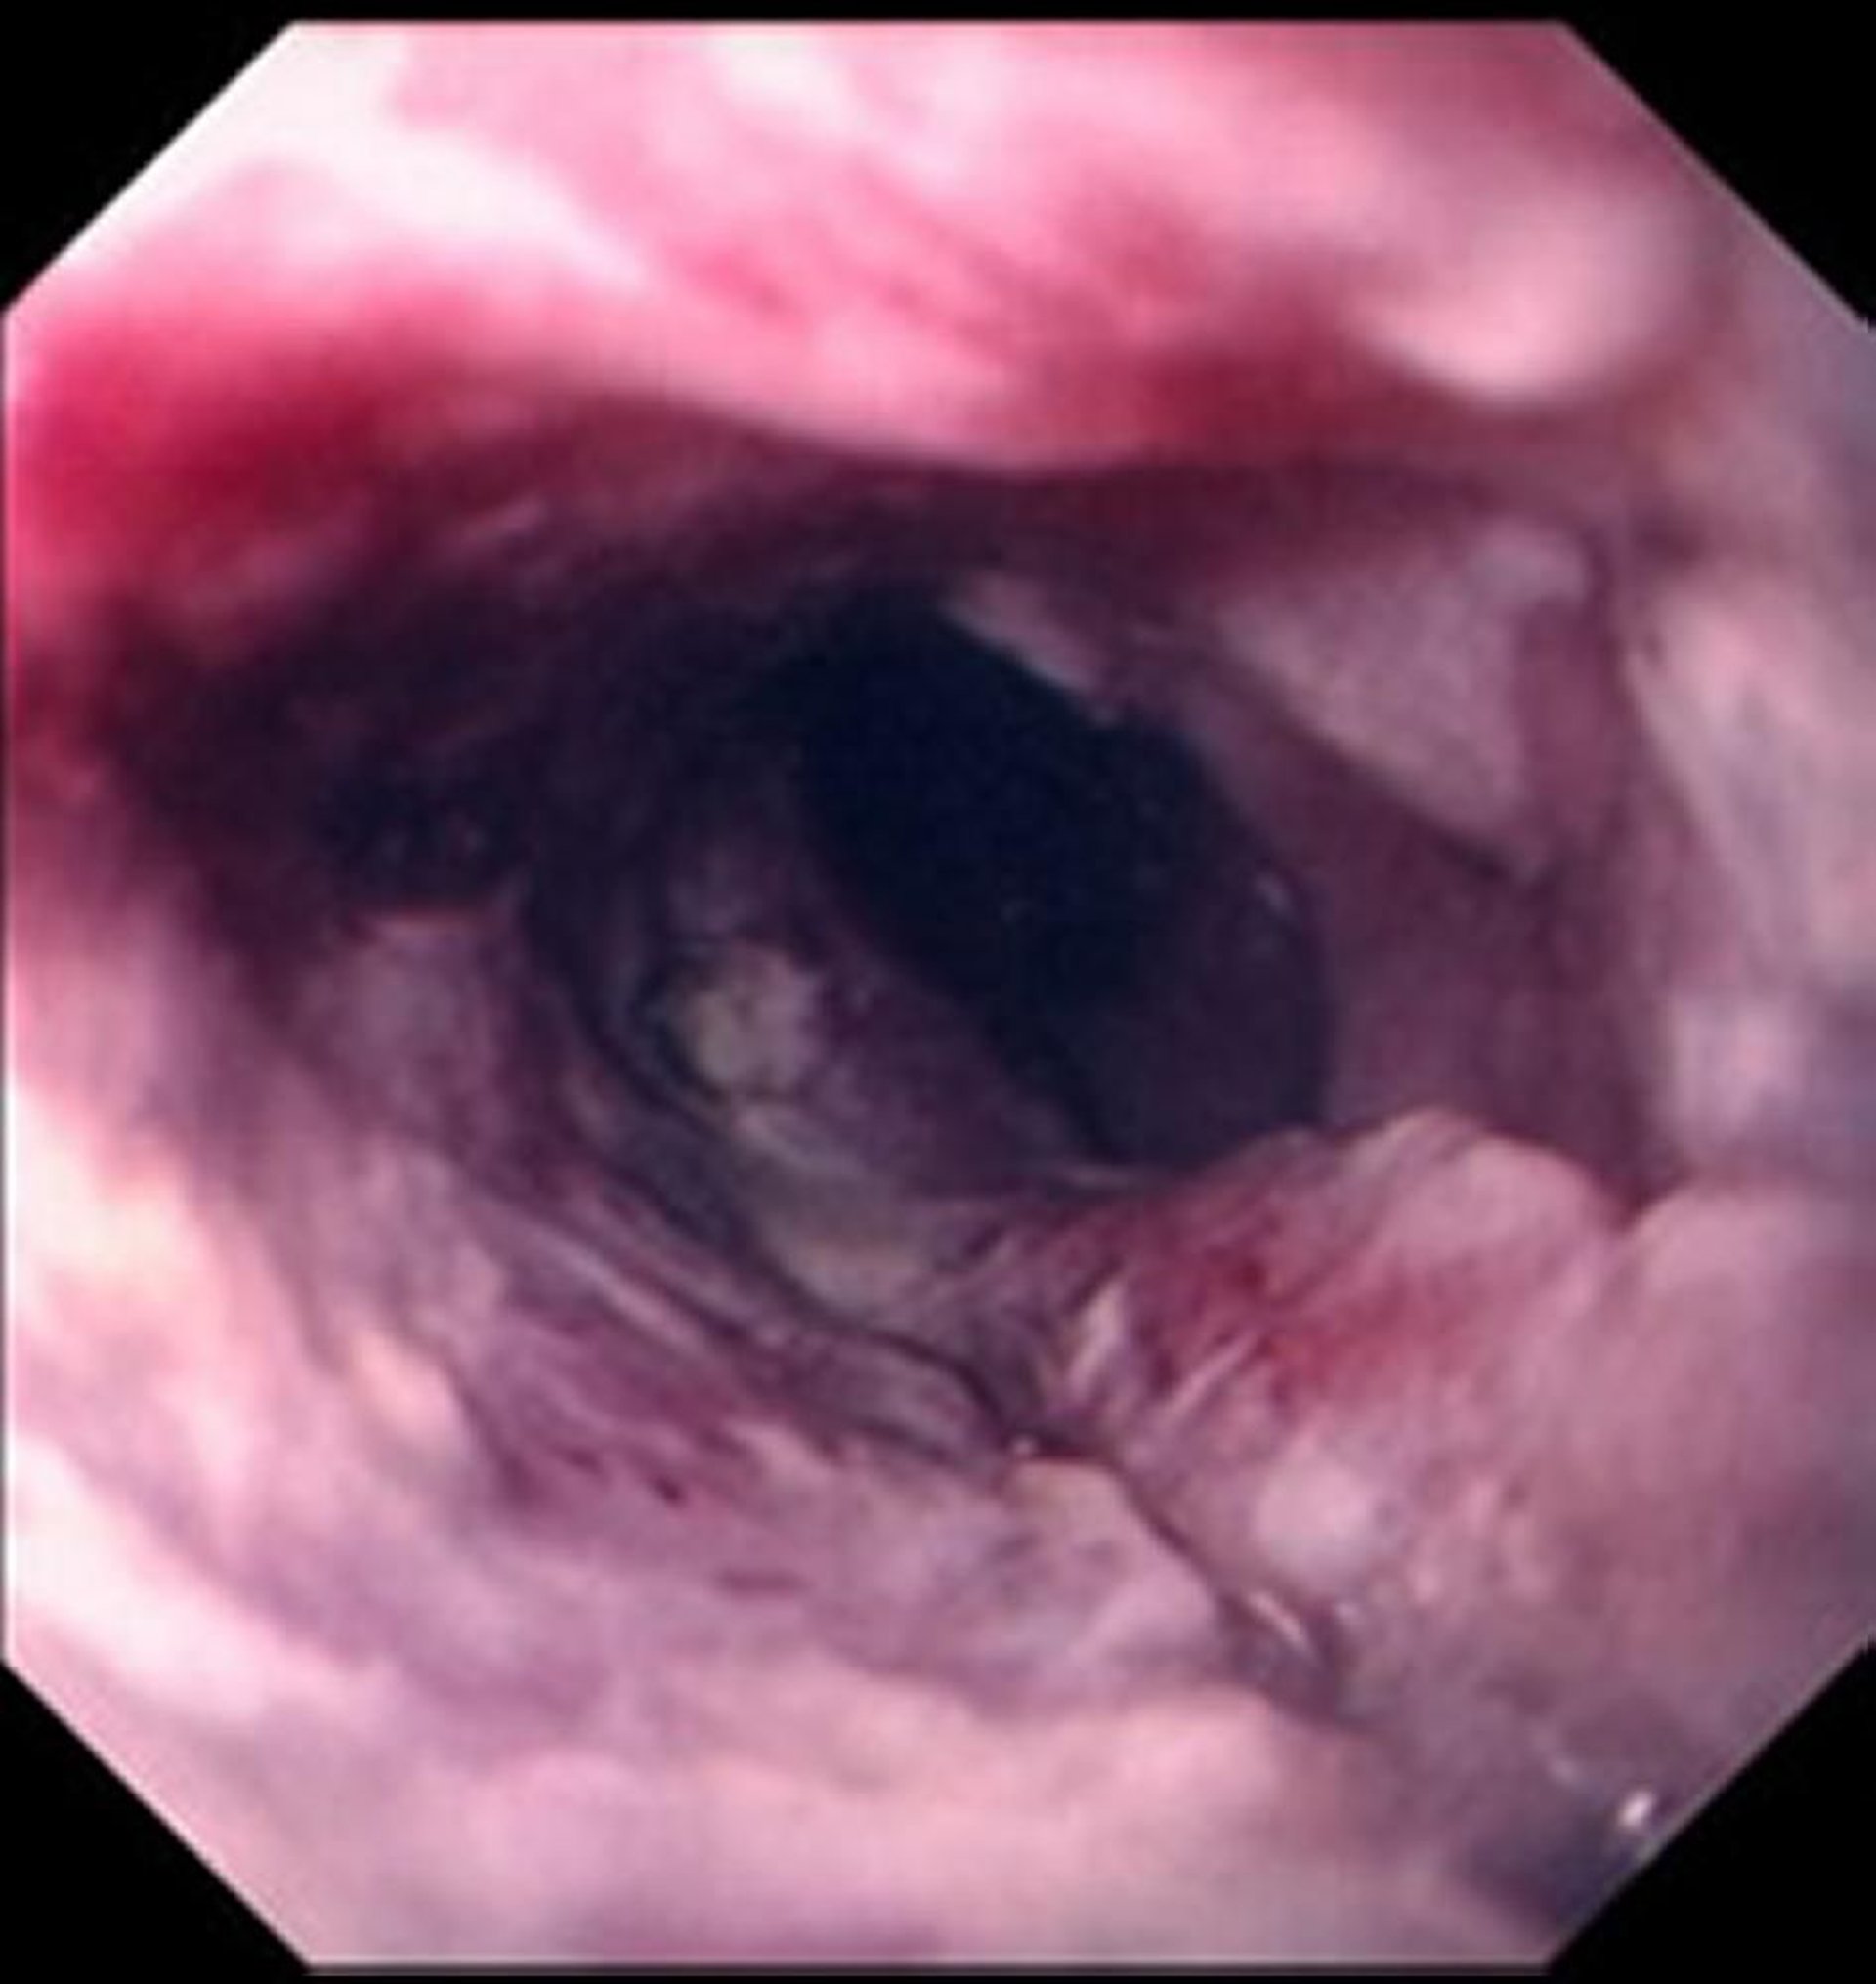

Carcinoma epidermoide de esófago

Por lo general, el carcinoma epidermoide se manifiesta por una masa ulcerada, irregular, que compromete la luz del esófago.

Images provided by David M. Martin, MD.